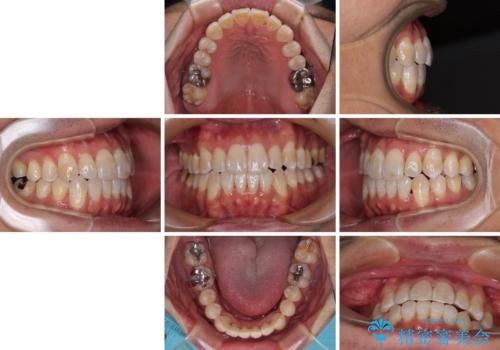

- 前歯のデコボコとクロスバイトを気にして来院された患者様です。

40代半ばであり、あまり周りに気を遣われずに治療を進めたいとのことで、インビザラインにて矯正治療を行うこととしました。

毎日22時間の装着時間をきっちりと守ってくださり、1年半かけずに思い通りの歯列に仕上げることができました。